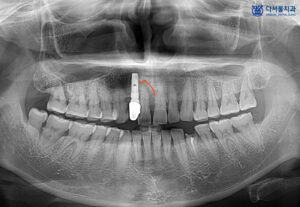

파노라마 사진을 살펴보면 전반적으로 중증도의 치조골 흡수가 있고, 파노라마 사진에서도 보일 정도의 잇몸 아래 치석이 확인되었습니다. 이로 인해 치아 주변으로 심한 골 흡수가 진행된 것으로 보였는데요. 옆의 임플란트에도 염증이 이환되어 제거를 고려해 보아야 했습니다.

흔들리는 앞니 옆 치아는 임플란트가 식립되어 있었으며, 임플란트까지 염증이 진행된 것으로 보였습니다. 또한 아래쪽 작은 어금니도 파절되어 있는 상태였습니다.